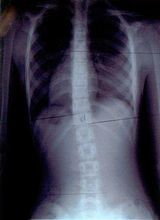

症例14)

信州大学12度→15度進行性、ここから当院通院で体操3ヶ月で6度に改善。

�@12歳 6年生 女子

平成19年6月 12度 信州大学病院 体操指導なし。

平成19年12月 15度 信州大学病院 体操指導なし。

�A平成20年1月27日 大塚整体 初診

側湾症改善大塚式鍛錬体操指導。

�B平成20年3月

6度

に改善正常範囲となる。定期検診は信州大学。

この2ヶ月間で2回体操指導。

レントゲンの比較で15度→6度の改善は明らかで脊柱がほぼ真っ直ぐです。

この時点で終了、自宅体操の継続を指導しました。

平成19年6月

経過観察

平成20年3月未検診

初診から体操2ヶ月後

12度

15度

6度 正常範囲